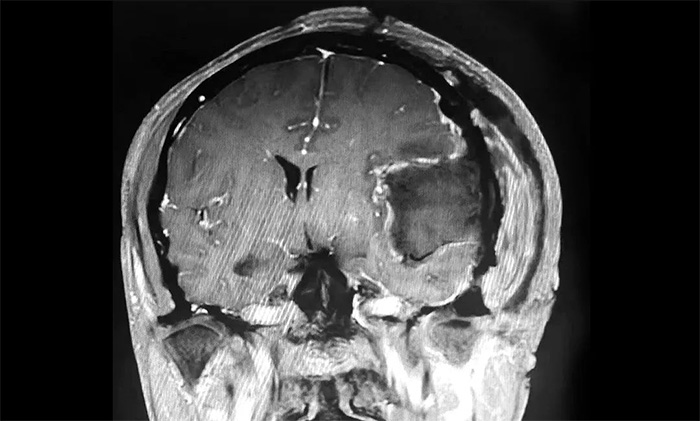

家人将其送往当地医院,经检查,肩胛骨骨折。进一步检查头颅CT,发现其左侧额颞部团块状高密度影,最大直径约6.0公分(厘米)。病灶体积巨大,患者来到上海蓝十字脑科医院寻求进一步治疗。

入院后,患者收治于神经内科4A病区。完善针对性检查后,经多学科综合会诊,患者左侧额颞部实性占位,最大直径约6.0公分,体积如鸭蛋大小,考虑左侧额颞部脑膜瘤。

▲ 肿瘤体积如鸭蛋大小

▲ 肿瘤顺利切除

手术取左侧额颞顶部入路,在显微镜下,沈建康主任与于耀宇主任通力协作,仔细分离肿物周边密集的神经血管,逐步分块切除肿物及附着的硬膜。切除肿瘤后,术区瘤腔未见活动性出血。历时5小时,手术顺利完成,留取病理标本送检。

术后,患者生命体征平稳,安返监护病房。经对留取的肿物样本进行病理分析,确定为纤维型脑膜瘤(WHO 1级),为良性肿瘤。